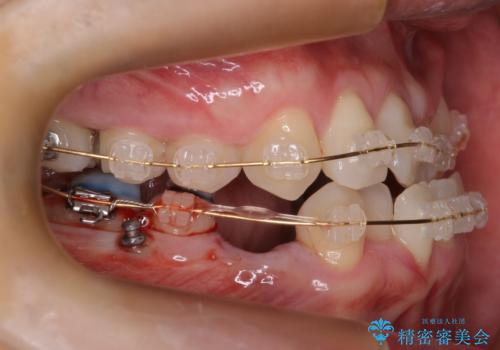

- 矯正装置

- 審美装置

- 治療期間

- 6年3ヶ月

- 治療回数

- 30回以上

かみしめもあり、骨も固く、歯根も長いためなかなか歯が動かず、患者様も治療する側も忍耐を要する長期戦となりました。